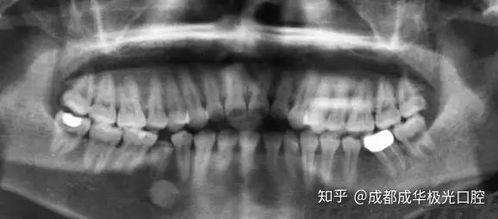

在正式开始拔牙之前,医生会先对你进行一系列的检查,确保你的口腔健康状况良好。这个过程,就像是一场精心编排的舞台剧,每个环节都至关重要。

首先,医生会给你戴上口罩,这是为了防止口腔内的细菌传播。接着,他们会用一种叫做“口镜”的工具,仔细观察你的牙齿状况。这个过程,就像是在用放大镜观察一颗颗宝石,每一个细节都不放过。